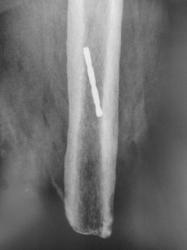

Иллюстрации 11, 12. В прямой стандартной проекции хорошо дифференцируется культя левой бедренной кости на уровне дистальной трети. Состояние культи удовлетворительное. На фоне бедренной кости чётко прослеживается тень металлического инородного тела – кусок сверла.